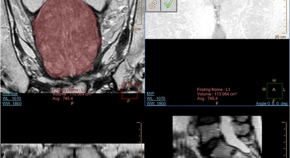

Spinal cord ischaemia is a rare complication following the gluteal injection of Benzathine benzylpenicillin. The hypothesis is embolization of the Penicillin products retrogradely through the Superior gluteal artery and cause occlusion of the vasculature that supply the spinal cord. This article includes literature review of the hypothesis behind the Spinal cord ischaemia and highlights the previous cases reported.